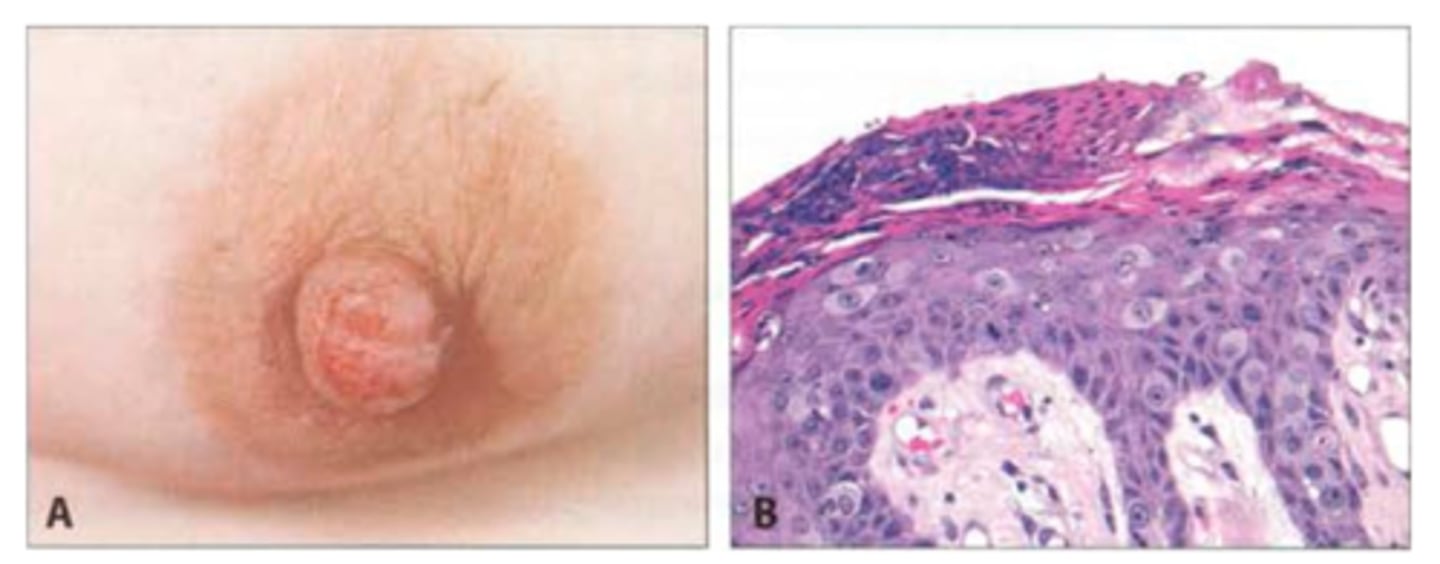

Red, itchy, swollen rash of nipple/areola

Paget disease of the breast (sign of underlying neoplasm)